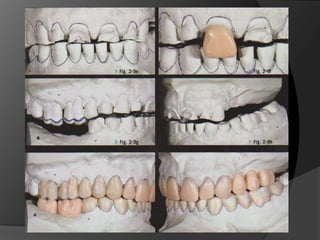

Diagnóstico y Planificación MultidisciplinariaHistoria ClínicaAnamnesisFotografía clínica Montaje modelos de estudioEncerados DiagnósticosEvaluación Radiográfica Radiografías PeriapicalesRadiografía PanorámicaEvaluación DentalEvaluación PeriodontalEvaluación EndodónticaEvaluación OclusalEvaluación Articular?

Diagnóstico y PlanificaciónMultidisciplinariaHistoria ClínicaAnamnesisFotografía clínica Montaje modelos de estudioEncerados DiagnósticosEvaluación Radiográfica Radiografías PeriapicalesRadiografía PanorámicaEvaluación DentalEvaluación PeriodontalEvaluación EndodónticaEvaluación OclusalEvaluación Articular?